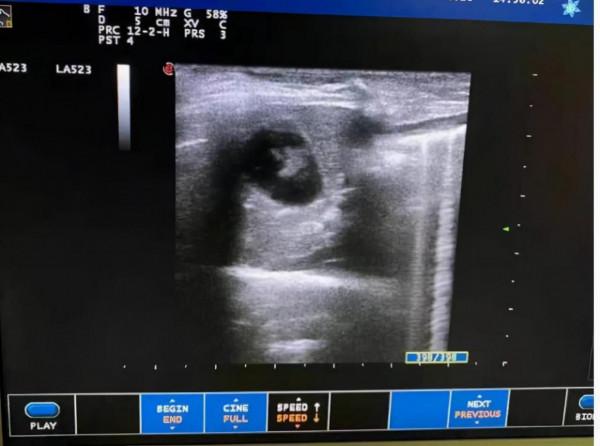

血液指標檢查顯示嗜酸性粒細胞數值為0,而b超檢查卻顯膽囊內可見大量高回聲沉澱物。結合茜茜的症狀及檢查結果確診茜茜患有泥沙樣的膽結石。主治醫生考慮到膽汁酸具有親脂性,可以溶解膽泥中的脂溶性物質,並且還能幫助肝臟合成分泌大量的稀薄膽汁沖刷膽囊,幫助膽泥排出。因此只使用了膽汁酸來幫助茜茜排膽泥,並要求茜茜2周後來醫院複查。